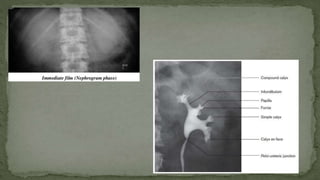

Pelvicalyceal arrangement:

➢ There are usually seven pairs of minor calyces, each

pair having an anterior and a posterior calyx, although

there is wide variation

➢ Minor calyx pairs combine to form two or three major

calyces, which in turn drain via their infundibula to the

pelvis.

➢ This arrangement is quite variable, but when there are

two infundibula these usually drain four pairs of calyces

from the upper pole and three pairs from the lower.

➢ When there are three infundibula there are usually

three pairs of upper pole calyces, and two sets of two

pairs of calyces draining the midpolar region and lower

pole.

➢ A simple calyx has one papilla indenting it; a

compound calyx has more than one.

Intravenous urography:

➢ After opacification by intravenous contrast, the renal

parenchyma and outline can be assessed in the early

or nephrographic phase, and the collecting system and

ureteric anatomy in the urographic phase

➢ In the urographic phase the calyceal system can be

seen. Minor and major calyces are seen. These are

connected to the pelvis of the kidney by infundibula ,

which may be long or short.